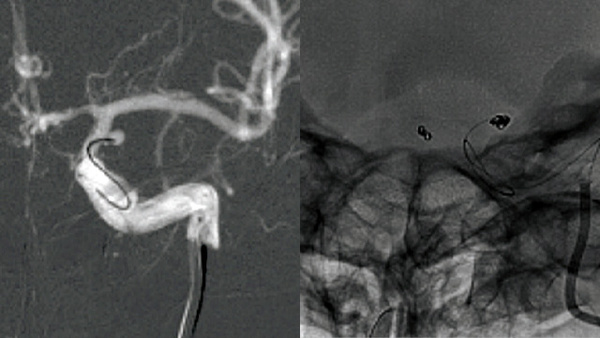

Retrieval of herniated coil during stent-assisted coiling

Find out how Dr. Nanthiya Sujijantarat (Departments of Neurosurgery and of Radiology & Biomedical Imaging, Yale University, New Haven CT, USA) treated a 45-year-old male patient suffering a ruptured, giant, partially thrombosed R ICA termination aneurysm.

• 45-year-old male patient presents with a ruptured, giant, partially thrombosed R ICA termination aneurysm.

• A first coil was inserted and detached. However, attempts to place a 2nd coil resulted in kickback of the microcatheter tip outside the aneurysm and into the stent.

• The microcatheter could not be tracked back inside the aneurysm over the partially deployed coil and attempts to remove the coil resulted in stretching of the coil tail (proximally) – almost as if the coil was tethered between the tines of the stent.

• The microcatheter tip is now in the cavernous ICA. Removal of the microcatheter resulted in further stretching and detachment of the coil.

• The force of injection carries the herniated coil tail (still stuck in the aneurysm) against the stent.

• If you look closely, you can see the stretched coil going into the tip of the guide catheter in both AP and lateral views.